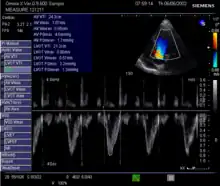

Echocardiography is a non-invasive method of quantifying cardiac output using ultrasound. Two-dimensional (2D) ultrasound and Doppler measurements are used together to calculate cardiac output. 2D measurement of the diameter (d) of the aortic annulus allows calculation of the flow cross-sectional area (CSA), which is then multiplied by the VTI of the Doppler flow profile across the aortic valve to determine the flow volume per beat (stroke volume, SV). The result is then multiplied by the heart rate (HR) to obtain cardiac output. Although used in clinical medicine, it has a wide test-retest variability.[9] It is said to require extensive training and skill, but the exact steps needed to achieve clinically adequate precision have never been disclosed. 2D measurement of the aortic valve diameter is one source of noise; others are beat-to-beat variation in stroke volume and subtle differences in probe position. An alternative that is not necessarily more reproducible is the measurement of the pulmonary valve to calculate right-sided CO. Although it is in wide general use, the technique is time-consuming and is limited by the reproducibility of its component elements. In the manner used in clinical practice, precision of SV and CO is of the order of ±20%.